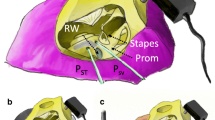

Understanding the complex mechanisms of bone conduction is crucial in improving the efficacy of bone-anchored hearing aids (BAHAs) for patients with unilateral hearing loss. BAHAs transmit sound to the contralateral ear, which helps overcome the head shadow effect and improves speech understanding1. Bone conduction mechanisms are complex and influenced by several factors, including signal frequencies. The suture of the skull can cause deformation of vibration patterns2, while bone thickness and density can impact sound propagation direction and vibration amplitude3. Ossicles play a role in bone conduction through piston or hinge movement, depending on the sound level4. Moreover, soft tissue in the skull also plays a significant role in bone conduction5,6,7,8. To optimize the effectiveness of BAHAs, understanding how sound reaches the contralateral ear is essential.

The contralateral bone conduction (BC) occurs through four different sound wave propagation mechanisms: (1) tangential and (2) normal to the skull bone surface, (3) rigid-body motion, and (4) direct propagation through the cerebrospinal fluid and brain tissue9. The dominant mechanism for contralateral bone conduction (BC) occurs through the skull bone when sound vibrations travel to the opposite side10,11. Stimulation of the mastoid initiates a vibration journey that can take various paths through the thin bony shell of the skull vault, thick skull base, or interior of the skull to reach the opposite ear12. The nature of cranial vibration modes varies according to the frequency range13. At around 300 Hz or below, the skull moves in a rigid body motion. For frequencies between 300 and 1000 Hz, the dynamics of the skull are a mass-spring system. At 1000–2000 Hz, there is a transition from a mass-spring system to a wave transmission. Above 2 kHz, the primary longitudinal wave transmission is primarily in the skull base and involves a mixed mode with a bending wave motion.

The results of the measurements revealed a significant acceleration amplitude in the mid-frequency range at the facial points as well as at the back and upper regions of the head. This finding suggests that the contralateral bone conduction efficiency was high at the front of the face. These results, particularly at the frequencies related to higher mode, were in line with the transcranial attenuation of vibrations reported in a previous study8. The observation that sound propagation is efficiently transmitted not only to skull bones but also to facial bones provides valuable information for the application of bone conduction implants (BCIs) in patients with unilateral hearing loss. Moreover, the position that showed the highest level of response is an efficient location for transmitting or monitoring stimuli to the opposite mastoid.

It has been observed that the efficiency of bone conduction is reduced and the phase dispersion is greater at the chin, which may be due to the bone's structure and thickness. Unlike other parts of the skull, the jawbone is connected to the skull through a joint and is not firmly attached to the upper part of the skull. Additionally, it is thicker than other parts of the skull, and the mandibular bone, in particular, is relatively thick and has a temporomandibular joint that lowers the efficiency of bone conduction. According to a study by Eeg-Olofsson et al., the squamosal sutures between skull bones can affect sound transmission through bone conduction, resulting in an average damping effect of approximately 2 dB for frequencies above 2 kHz8. The efficiency of bone conduction depends on the thickness of the bone and its distance from the cochlea, and bone thickness can affect the frequency specifications of various pathways involved in hearing. Sohmer et al. reported that the threshold for bone conduction was lower when vibration was applied to the thin temporal bone than when applied to the thick forehead section of a dried cadaver16. Similarly, this experiment showed the lowest vibration efficiency in the thickest bone, which is the chin.